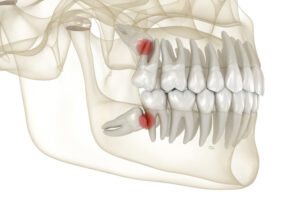

Chirurgie endodontică: Salvarea dinților cu infecții la rădăcină (rezecții apicale) atunci când tratamentele clasice de canal nu mai sunt suficiente.

Extracții dentare complexe: Îndepărtarea dinților afectați grav de carii sau inflamații, dar și a molarilor de minte care nu au loc să erupă corect (incluzii dentare).